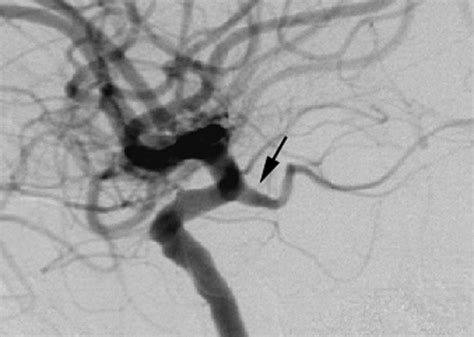

Clinical Significance: Posterior Communicating Artery Aneurysms

One of the most clinically significant aspects of this vessel is its susceptibility to aneurysm formation. Because of its location and the hemodynamic forces exerted at its junction with the internal carotid artery, the Posterior Communicating Artery is a frequent site for intracranial aneurysms. These aneurysms are particularly dangerous because they are often located in close proximity to the oculomotor nerve (cranial nerve III).

When an aneurysm develops here, it may exert pressure on the oculomotor nerve, leading to specific symptoms that act as a medical warning sign. These symptoms can include:

Imaging and Diagnostic Approaches

To visualize the Posterior Communicating Artery and assess its patency or detect potential pathology, clinicians rely on advanced neuroimaging techniques. Modern diagnostics allow for a detailed view of the cerebrovascular anatomy without the need for invasive procedures in many cases.

• Digital Subtraction Angiography (DSA): Considered the gold standard, this invasive procedure involves injecting contrast dye directly into the arteries to provide the highest resolution images of the PCoA and its branches.